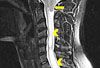

A 37-year-old man was brought to the emergency department (ED) after he had 2 near-syncopal events. The first occurred in the morning and rapidly resolved; the second occurred later in the day at work. The night before he had a headache and neck pain. In the ED, he reported left arm and leg weakness and was noted to have left facial droop.